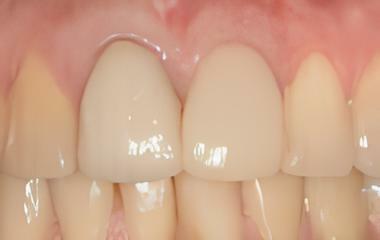

IMPLANTOLOGIE: LES IMPLANTS DANS LE SECTEUR ESTHÉTIQUE